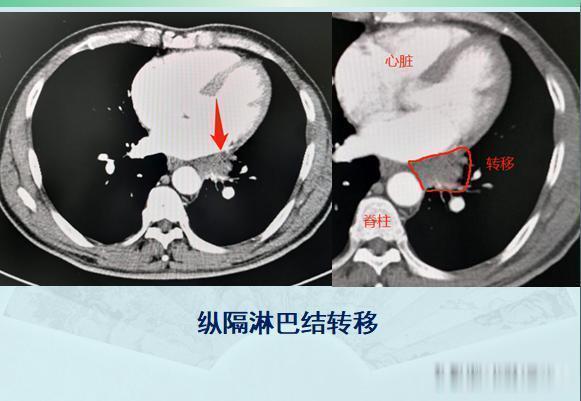

增强CT显示肿块轻度不均匀强化,同时还发现了纵隔淋巴结肿大,符合肺癌,而且他已经没有手术机会了。同样是拖了两年,这位病人的运气就没有第一位老太太那么好!

后来老人做了经皮肺穿刺,病理是小细胞肺癌。实际上CT图像也提示小细胞肺癌的诊断:1.原发灶比较光滑,像土豆一样,可以有浅分叶,血供不丰富所以轻度强化;2.小细胞肺癌对血管破坏比鳞癌轻,很少发生大片坏死,所以空洞少见;3.小细胞肺癌转移早,原发灶较小时就常见肺门及纵隔淋巴结多发转移,从而失去手术机会;4.与吸烟关系密切。不过幸运的是,这位老人的肺癌对化疗很敏感,做了两个周期的化疗(依托泊苷+奈达铂)后复查,病灶明显缩小,纵隔淋巴结也萎缩了: